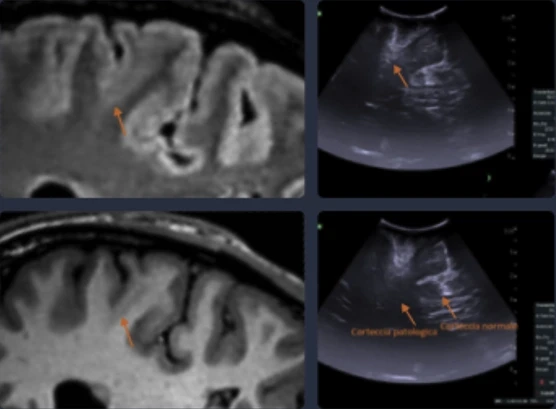

A 12-year-old boy in Florida endured daily seizures and repeated misdiagnoses despite numerous tests. Doctors missed a rare condition of Focal Cortical Dysplasia (FCD).

Advanced AI analysis of his MRI could have revealed the cause sooner, transforming life for him and his family.